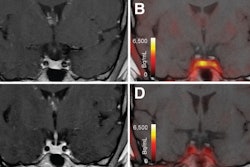

- Enhanced therapeutic opportunities. Theranostics has opened new horizons for nuclear medicine, such as targeted radionuclide therapy, which can be used to treat e.g., prostate cancer and thyroid disorders. Close cooperation allows for seamless integration of high-resolution diagnostic imaging data (anatomical targets) with functional data (treatment response assessment and optimized therapy delivery).

- Improved patient management. Collaboration will streamline patient management workflows, e.g., optimized scheduling, reduced wait times, and enhanced overall efficiency. It will allow for integrated diagnostic reports with findings from both disciplines and facilitate informed decision-making and personalized treatment strategies. Also, it will ensure new and exciting developments such as theranostics aren't hijacked by clinicians and organ specialists, who may lack the profound understanding of anatomy and pathophysiology needed to treat patients adequately.

The bone of contention has everything to do with the growing role of theranostics, i.e., radioligand therapy which uses the same target for both imaging and treatment. Theranostics has the potential to become a game changer in cancer care. However, there is a very real concern that theranostics may be taken over by specialists in radiation oncology, urology, oncology, neurology, and endocrinology. Close collaboration between diagnostic imaging and nuclear medicine specialists provides the best opportunities for patient-centered workflows and integrated care. This view is often not shared by medicine physicians, most of whom would prefer to collaborate with clinicians and ‘embed’ theranostics within an oncologic practice.

When two dogs fight for a bone, a third may run away with it, and I am very much afraid this could happen with theranostics. While radioligand therapy offers great opportunities for patients, setting up the infrastructure does pose a challenge to healthcare authorities and payers. A strong alliance between diagnostic imaging and nuclear medicine can assist in careful patient selection, streamlined workflows and optimized patient care, with the ability to assess treatment results through quantifiable imaging biomarkers. These opportunities could be lost in a ‘vertically integrated’ model, with oncologists or organ specialists controlling and managing the treatment.